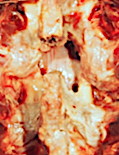

En este caso se ha realizado un abordaje derecho típico de una microdiscectomía, con resección de lámina superior, receso lateral y foramen

Visión cenital del abordaje anterior